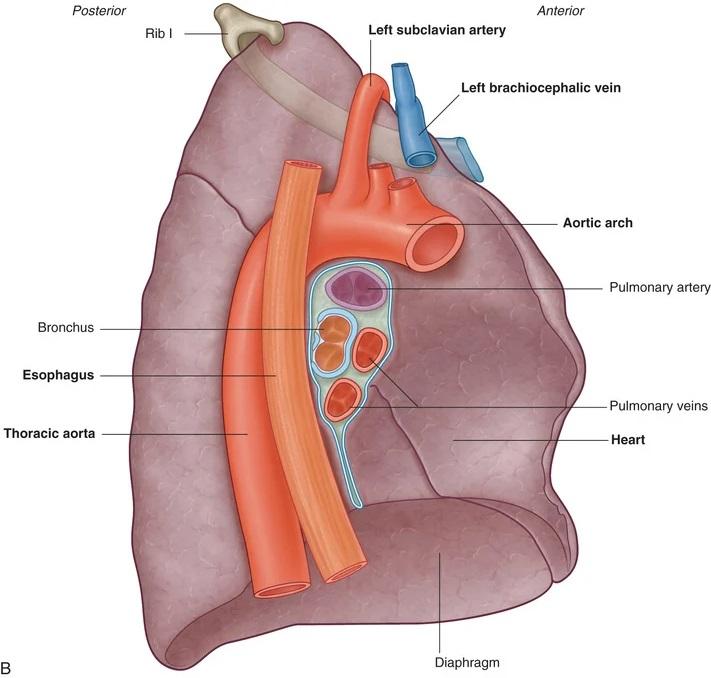

Fig 3.38b: Longhilus links

aorta a. pulmonalis sinistra vv. pulmonales (zwart) bronchus

Grays: Fig 3.46